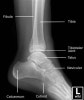

소아 발목의 X-ray2017-02-26카테고리 103원본 보기 Ankle Paediatric Protocol : AP, Lateral Ankle AP view Ankle Mortise view Ankle Lateral view ← 이전 글소아 무릎, 아래 다리의 X-ray다음 글 →발목관절 골절(Salter-Harris fracture)같은 카테고리 글2017-02-25소아 무릎, 아래 다리의 X-ray2017-02-18소아의 골반, 고관절, 대퇴골의 X-ray2017-02-14손목 성장판 골단판 골절(Epiphysiolysis fracture)← 전체 글로 돌아가기